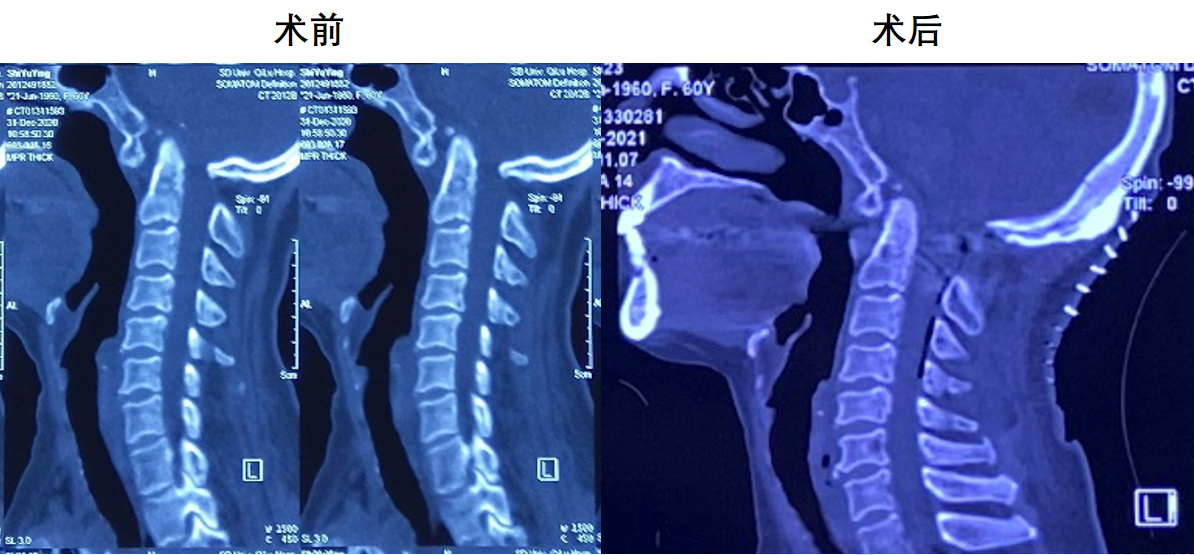

颈椎CT:

颈椎退行性变,C2/3、C3/4、C4/5、C5/6、C6/7椎间盘突出并C4/5水平椎管狭窄;符合颅底凹陷症合并寰枕融合,寰枢关节脱位CT表现。

术后复查枕颈X线、CT、MR结果

影像学检查显示齿状突复位良好,脊髓减压充分